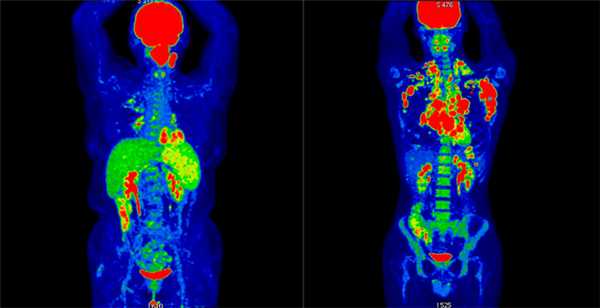

Результаты ПЭТ/КТ-исследования. Слева: неходжкинская лимфома (поражение левой небной миндалины и селезенки, поражение лимфоузлов выше диафрагмы. Справа: ходжкинская лимфома (поражение лимфоузлов по обе стороны от диафрагмы, с тенденцией к слиянию в массивные конгломераты, наиболее крупные в подмышечной области слева и в лимфоузлах средостения справа. III стадия)

Наиболее информативным методом определения стадии и агрессивности заболевания является ПЭТ/КТ. КТ и МРТ также используют для диагностики, но с их помощью сложно отличить злокачественный процесс от доброкачественных изменений, а оценка распространенности процесса занимает больше времени, чем при ПЭТ/КТ.

Позитронно-эмиссионная томография позволяет провести анализ метаболических процессов в клетках. Злокачественные опухоли поглощают питательные вещества интенсивнее обычных, это значит, что они накапливают больше радиофармпрепарата и хорошо видны на снимках как участки яркого свечения. КТ и МРТ показывают только структурные изменения органов, объективно оценить функциональное состояние клеток этими методами невозможно.

ПЭТ/КТ всего тела у пациентов с лимфомами

Для обследования пациентов с лимфомами применяют ПЭТ/КТ всего тела с 18F-фтордезоксиглюкозой. Этот радиопрепарат распространяется по всем органам и тканям. За одно исследование врач получает изображение всех анатомических областей. Для достижения такого охвата при диагностическом КТ нужен анализ серии исследований различных областей тела, что увеличивает лучевую нагрузку на пациента.

По различным данным чувствительность ПЭТ/КТ диагностики может достигать 100% при диффузной В-крупноклеточной лимфоме, 98% при лимфоме Ходжкина и фолликулярной лимфоме, 67% при формах, поражающих зону мантии, 95% при миеломной болезни. Обследование наиболее результативно в случаях, когда клетки лимфомы характеризуются повышенной активностью, то есть при болезни Ходжкина и неходжкинских лимфомах высокой степени злокачественности.